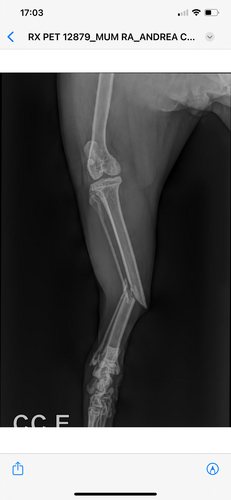

Este acidente ocasionou muitas lesões como: fratura de fêmur, deslocamento de bacia, fratura de cauda e perda de controle fisiológico.

Diante dessa situação, ele terá que passar por uma cirurgia de grande porte para estabilizar sua situação, nesta cirurgia ele colocará pinos na pata e removerá a cauda. Conseguimos um cartão de crédito para pagar as despesas mas está muito caro e precisamos de ajuda!